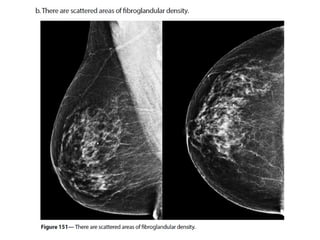

Breast imaging based on

ACR2013

MD .Dr.k.sharifi.radiologist